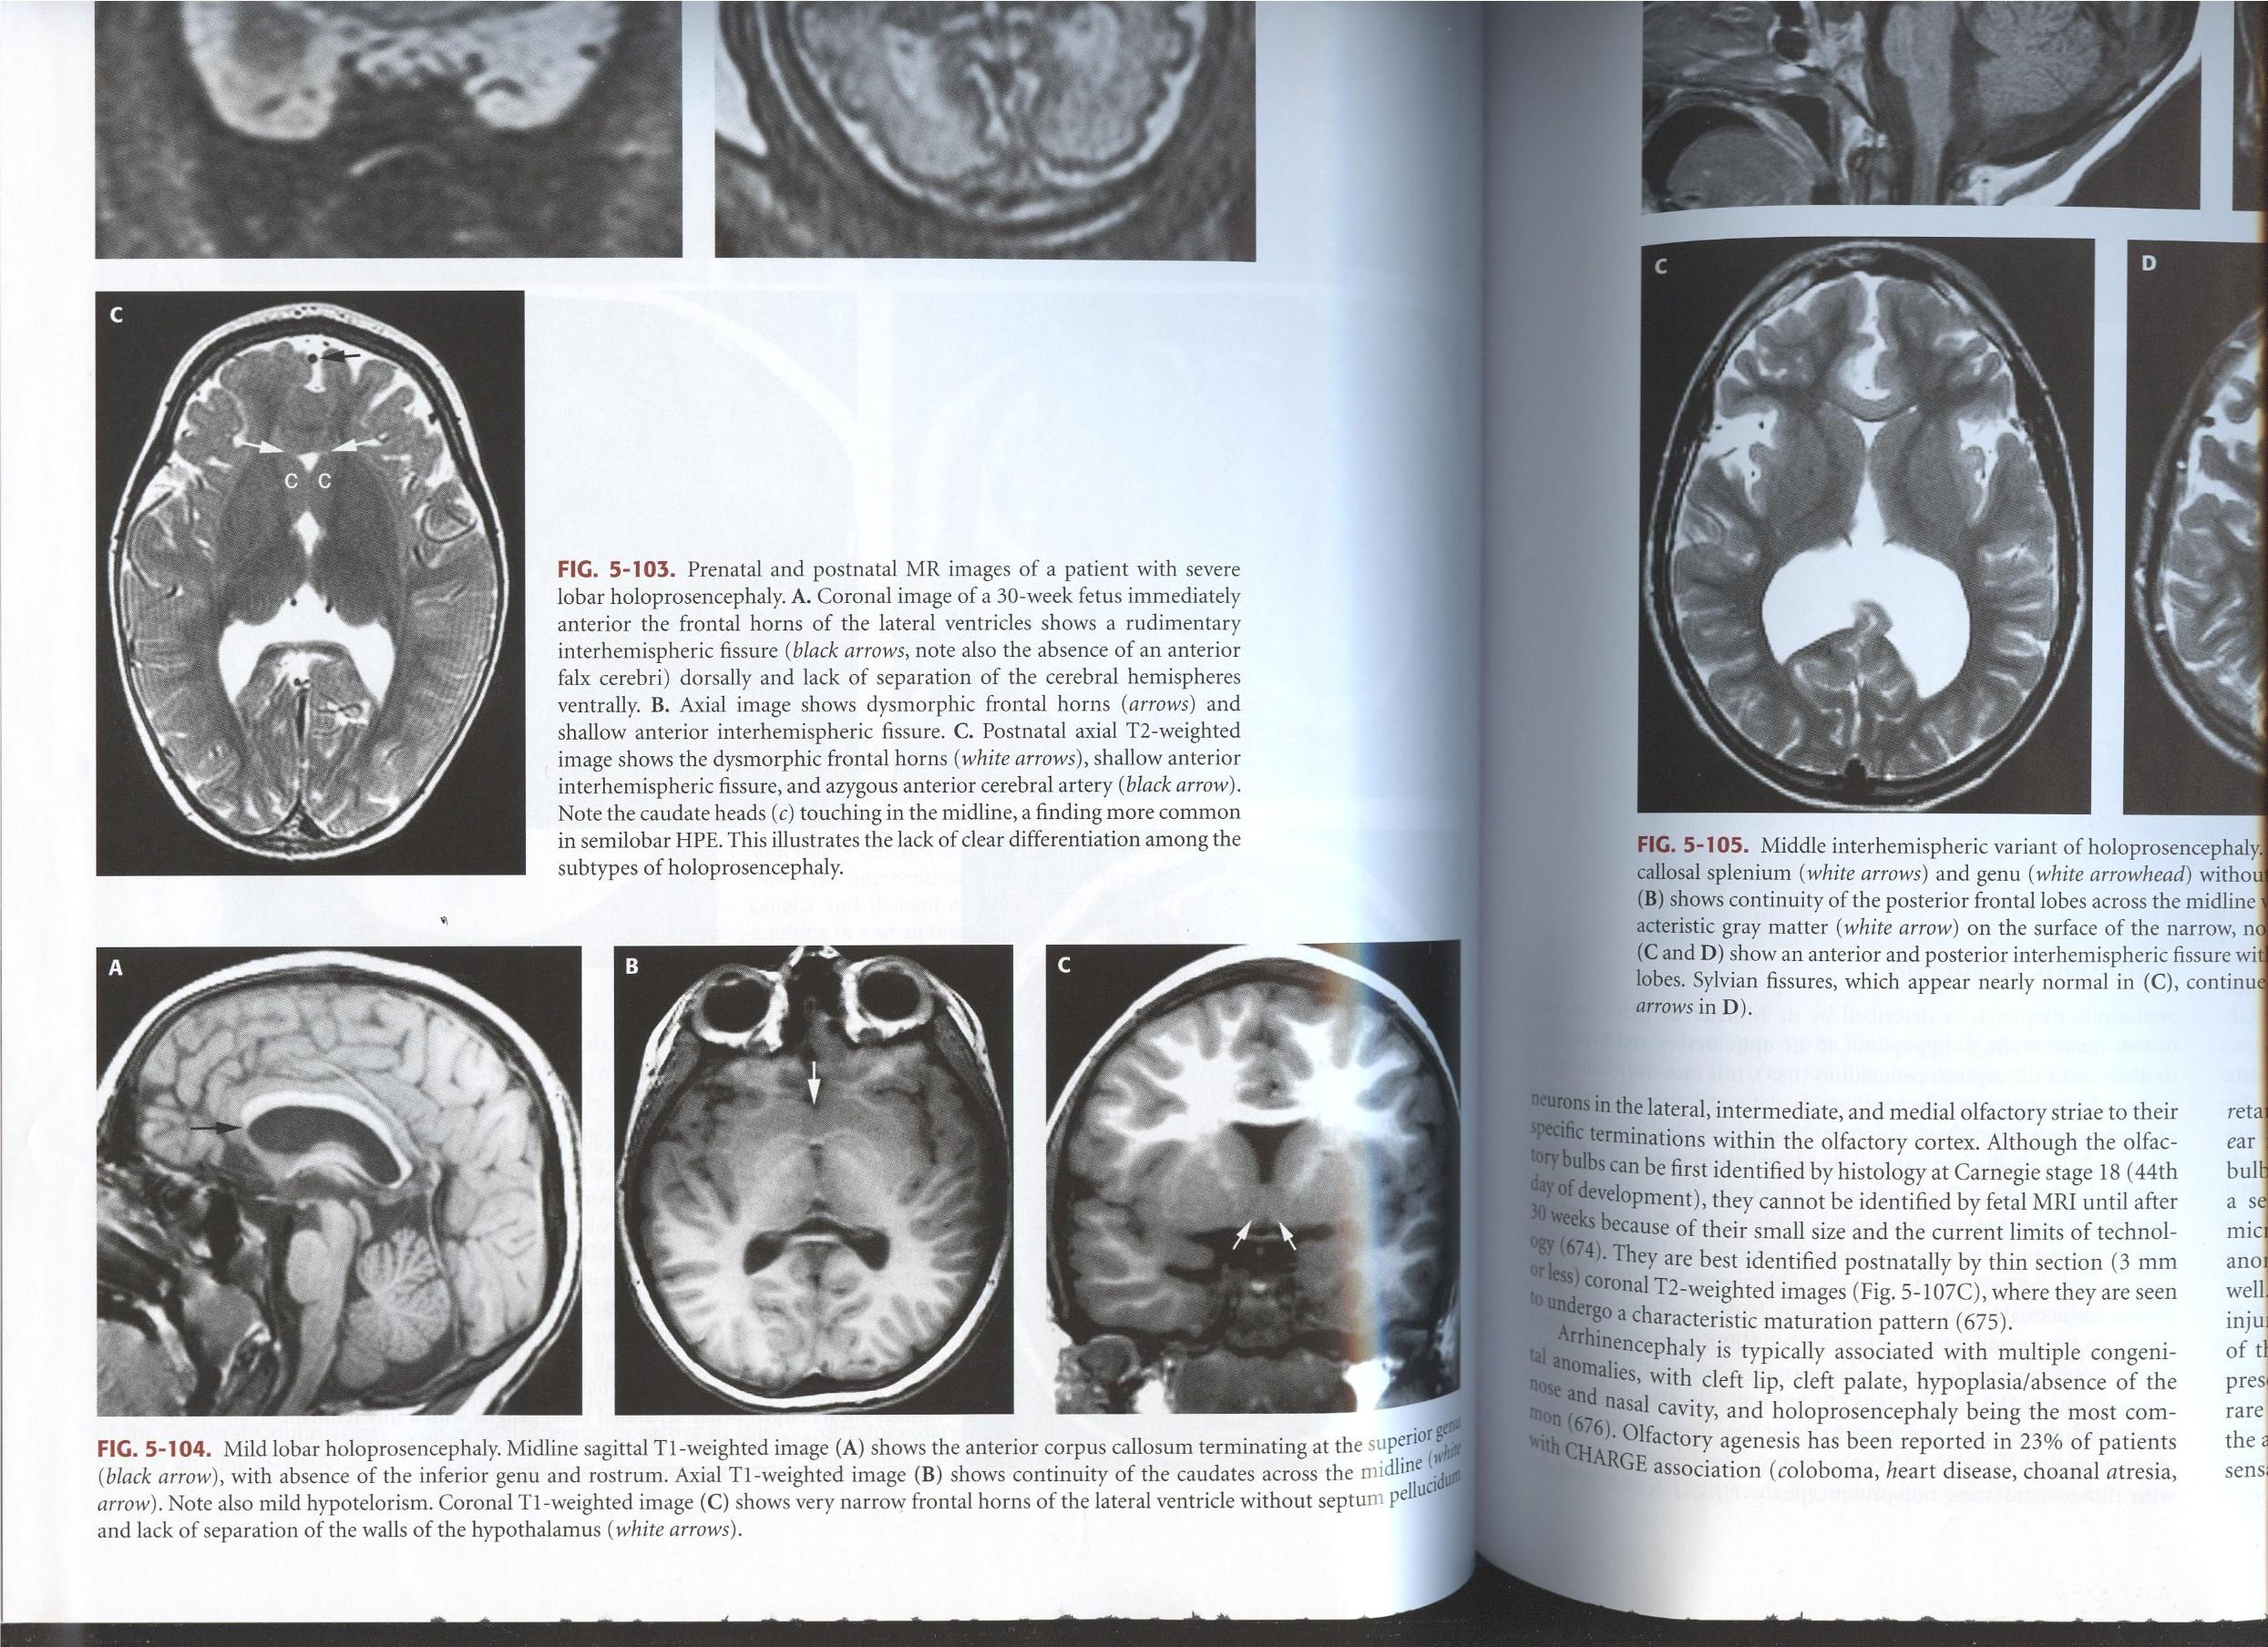

Alobar

Most severe, complete lack of “cleavage”, fused thalami.

Semilobar

“ in between” with separated occipital lobes

Lobar Mild, often only anterior frontal lobe fused, with separate thalami